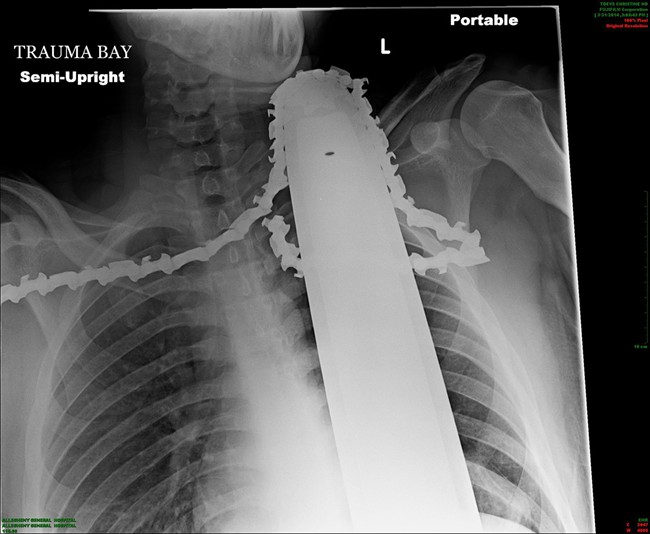

Valentine had emergency surgery at Allegheny General Hospital. Doctors say the saw missed major arteries and instead cut into muscle. The hospital Tuesday released an X-ray showing the saw still in the 21-year-old’s neck.